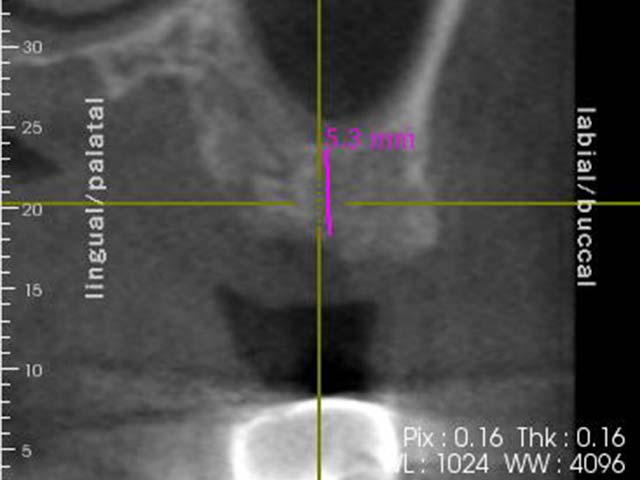

鼻竇增高術(垂直)+植牙 首頁 案例分享 人工植牙 鼻竇增高術(垂直)+植牙 鼻竇增高術(垂直)+植牙 術前評估 PRF(使用法國離心機,萃取出有益於傷口癒合的血小板,並加以濃縮) 鼻竇增高術 從植牙傷口置入萃取的PRF,將鼻竇往上抬升,再植入骨粉,以利植牙。 電腦斷層—術前,術中,假牙完成